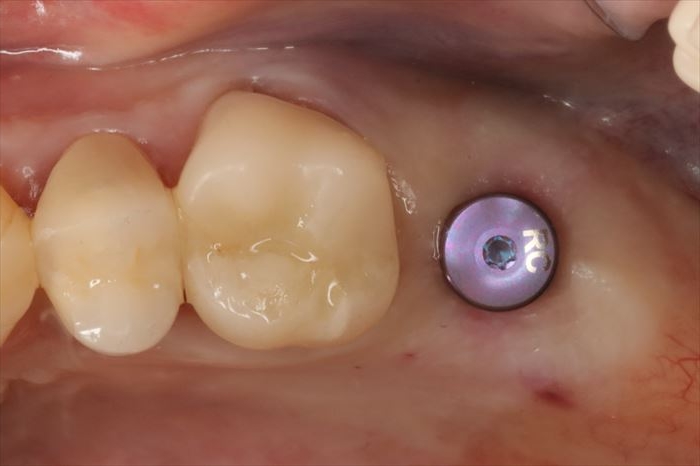

インプラントの埋入を終えました。

青い挿入ジグを外しましたら、インプラントネックが骨内に位置していることを顕微鏡下で確認します。

歯肉表面から最低でも約4㎜下にインプラントネックが位置するように調整します。

インプラントの位置付けが浅いことは私の中では絶対禁忌と考えています(私見です)

周囲の歯肉の形態を形成し、インプラント接続部分の保護のためのヒーリングキャップを用意します。

ヒーリングキャップを締結しました。

歯肉切開を伴わないフラップ(歯肉弁)レス埋入オペではオペ終了時に止血も完了します。